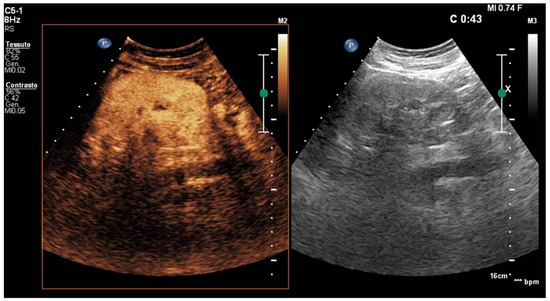

- Rinaldo, C.; Grimaldi, D.; Di Serafino, M.; Iacobellis, F.; Verde, F.; Caruso, M.; Sabatino, V.; Orabona, G.D.; Schillirò, M.L.; Vallone, G.; et al. An update on pyelonephritis: Role of contrast enhancement ultrasound (CEUS). J. Ultrasound 2023, 26, 333–342. [Google Scholar] [CrossRef]